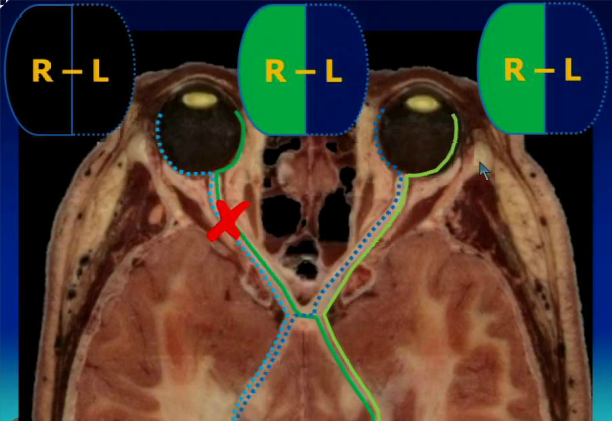

Which part of the eye field is seen by the right occipital lobe? The left?

The right occipital lobe sees the left half of the eye field in each eye and the left occipital lobe sees the right half of the eye field in each eye.

A patient comes to the ED after a car accident. She hit her head on the dashboard and can now no longer see anything from her left eye. Where is the lesion in the optic tract?

She has a lesion proximal to the optic chiasm, causing monocular blindness.

A patient presents complaining that she can never see their kids sneaking up on the side of her. Where in the optic tract does she have a lesion?

Optic chiasm. She has bitemporal hemianopsia. Remember that the image coming from the temporal nerve transmits stimuli from the nasal field.